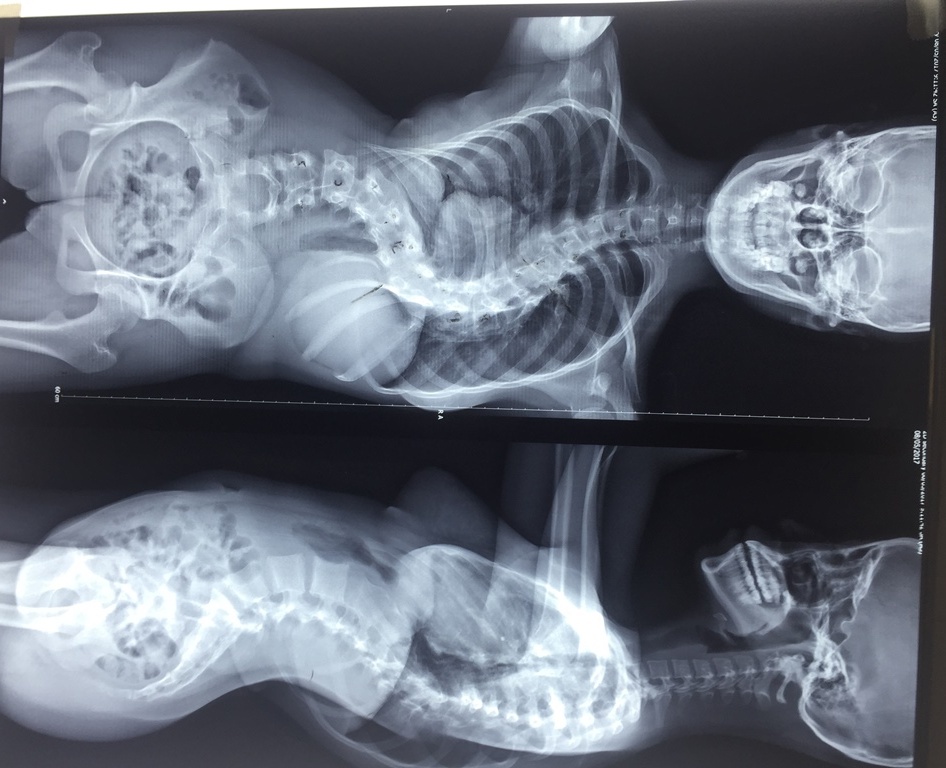

| Phim chụp X-quang hình ảnh cột sống của bệnh nhân. Ảnh: Hoài Nhơn |

Ngày 5/1, Bệnh viện Trưng Vương (TP.HCM), vừa phẫu thuật thành công cho Lê Quỳnh Như (15 tuổi, quê Kiên Giang) bị cong vẹo cột sống lên đến 110 độ. Bệnh nhân mắc hội chứng Marfan làm vẹo cột sống, khó thở gây nhịp tim nhanh.

Cách đây 4 năm, bệnh nhân được phát hiện mắc bệnh khi cột sống bị cong vẹo khoảng 60 độ. Năm 2015, Như bắt đầu dậy thì, góc vẹo ngày càng tăng mặc dù đã được điều trị bằng cách mang nẹp.

Ngày 26/12/2017, ê-kíp bác sĩ đã thực hiện ca mổ kéo dài hơn 6 tiếng, chỉnh độ cong vẹo cột sống từ 110 độ còn 40 độ, nắn chỉnh trên 64%.